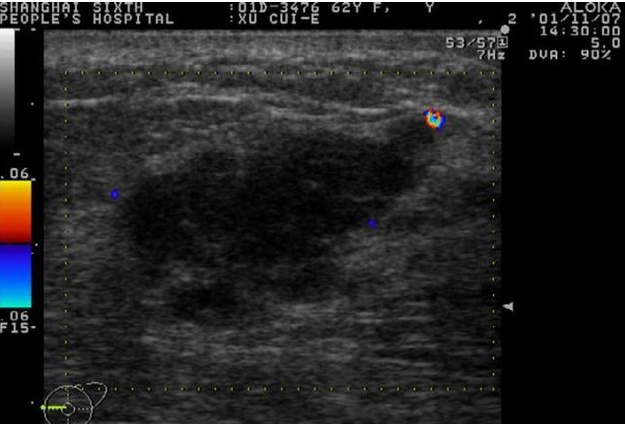

乳腺癌彩超报告单图片

早期乳腺癌b超报告图